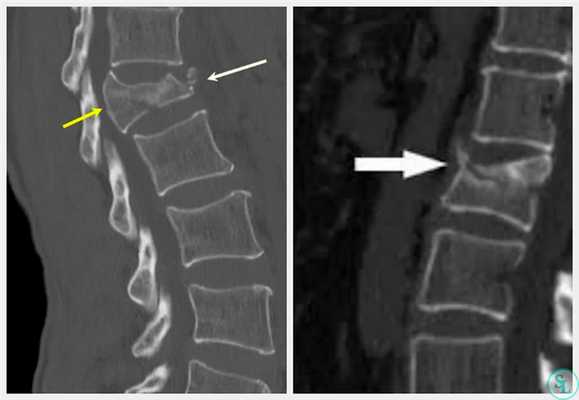

Пример лечения перкутанной транспедикулярной фиксацией спондилодисцита

После длительного курса лечения антибиотиками выполнена транспедикулярная фиксация системой viper II

Все осложнения, связанные с транспедикулярной фиксацией позвоночника погружными конструкциями следует схематично разделить на несколько групп (Николаев Н.Н., 2002; Усиков В.В., Усиков В.Д., 2006; Бублик Л.А. с соавт., 2007; Esses S.I., Sachs B.L., Dreyzin V., 1993; Schwab F.J., Nazarian D.G., Mahnmud F. еt al., 1995; Davne S.H., 1999):

Недооценка плотности фиксируемого (-ых) позвонка (-ов).

Недоучет индивидуальных особенностей позвонка, угла наклона ножки позвонка.